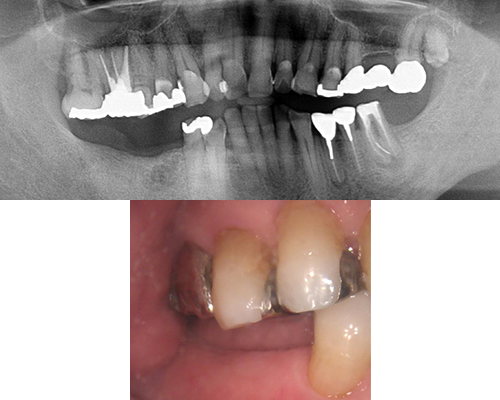

| 施術内容 | 右下の残存乳歯が保存困難なため抜歯。前後の歯が健全なため削らずに済むインプラント治療へ。 |

|---|---|

| 治療期間 | 8ヶ月(抜歯後治癒期間含) |

| 治療費 | 約40万円(ハイブリッドセラミック冠) |

| 副作用・リスク | インプラント治療は手術を伴います。腫れや痛みが少なくなるよう努力をしておりますが、多少の腫れや痛みが出ます。しかし、痛み止めで抑えられる程度ですのでご安心ください。 |

※表示は全て税込表示です。